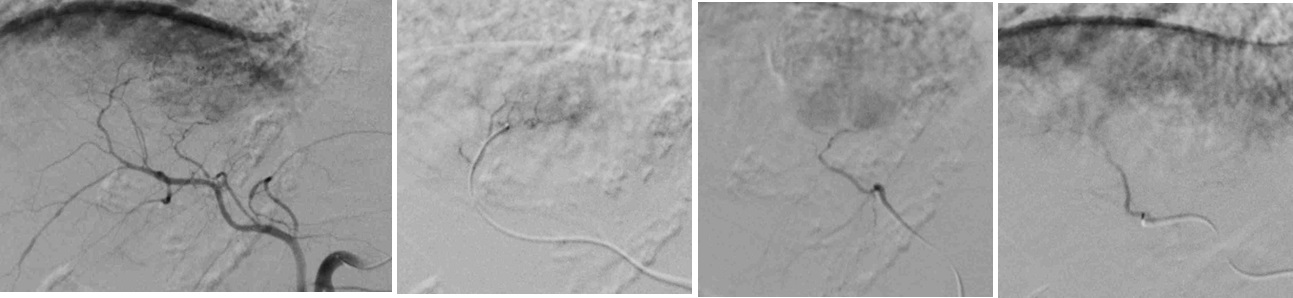

肝細胞癌はIVRに最も馴染みの深い癌で、標準治療の一つであるTACEはIVRの代名詞の一つとなっています。近年、肝細胞癌治療は複雑化しており、当IVR外来では、消化器内科とも連携し、TACEのみならず、RFA、動注療法、薬物療法などを取り扱います。是非、ご紹介ください。また、肝転移に対しても、同様の治療を行うことが可能です。

HCC TAE